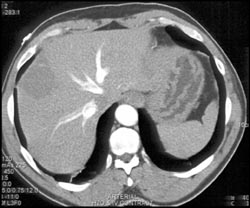

Diagnosis

Normal Arterial Anatomy